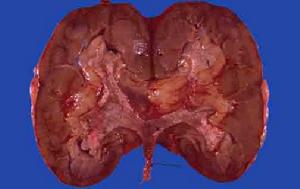

②乳頭狀癌:源於腎盂黏膜移行上皮的惡性腫瘤,呈單發或多發,呈乳頭狀生長,此癌先從腎盞向腎盂表面播散,隨後向下延及輸尿管或膀胱,約一半乳頭狀癌侵犯肌層、靜脈、淋巴管,遠處轉移達肺、肝、骨或入淋巴結。鏡下:癌以纖細的纖維血管束為核心作分枝狀排列,外被以未分化的多形性移行上皮,核染色質數量不等。該癌多由良性乳頭狀瘤惡變而來。凡乳頭變粗,變短,融合,瘤組織壞死,都系癌變表現。乳頭癌分浸潤性和非浸潤性兩種,非浸潤性乳頭狀癌與乳頭狀瘤的區別在於前者的瘤細胞失去正常柵狀排列的特點,瘤細胞大小、形狀、染色性質不一,核染色質豐富,出現大量核分裂等。浸潤性乳頭狀癌除上述特點外,還見癌細胞向固有膜或肌間浸潤。

③鱗狀細胞癌:少見。中老年患病,男女相等,大體標本見扁平隆起的腫塊,質硬脆,常在腎盂內擴展形成潰瘍。切面多呈灰白色,乾燥,50%的病例伴鈣化和感染,鏡下能見到鱗癌的一般表現。腫瘤可穿過腎盂壁並迅速轉移,常轉移到局部淋巴結、肺、肝及骨等處。